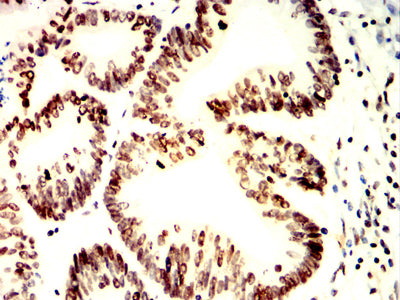

Immunohistochemical analysis of paraffin-embedded human colon cancer tissues using H2AFX mouse mAb with DAB staining.